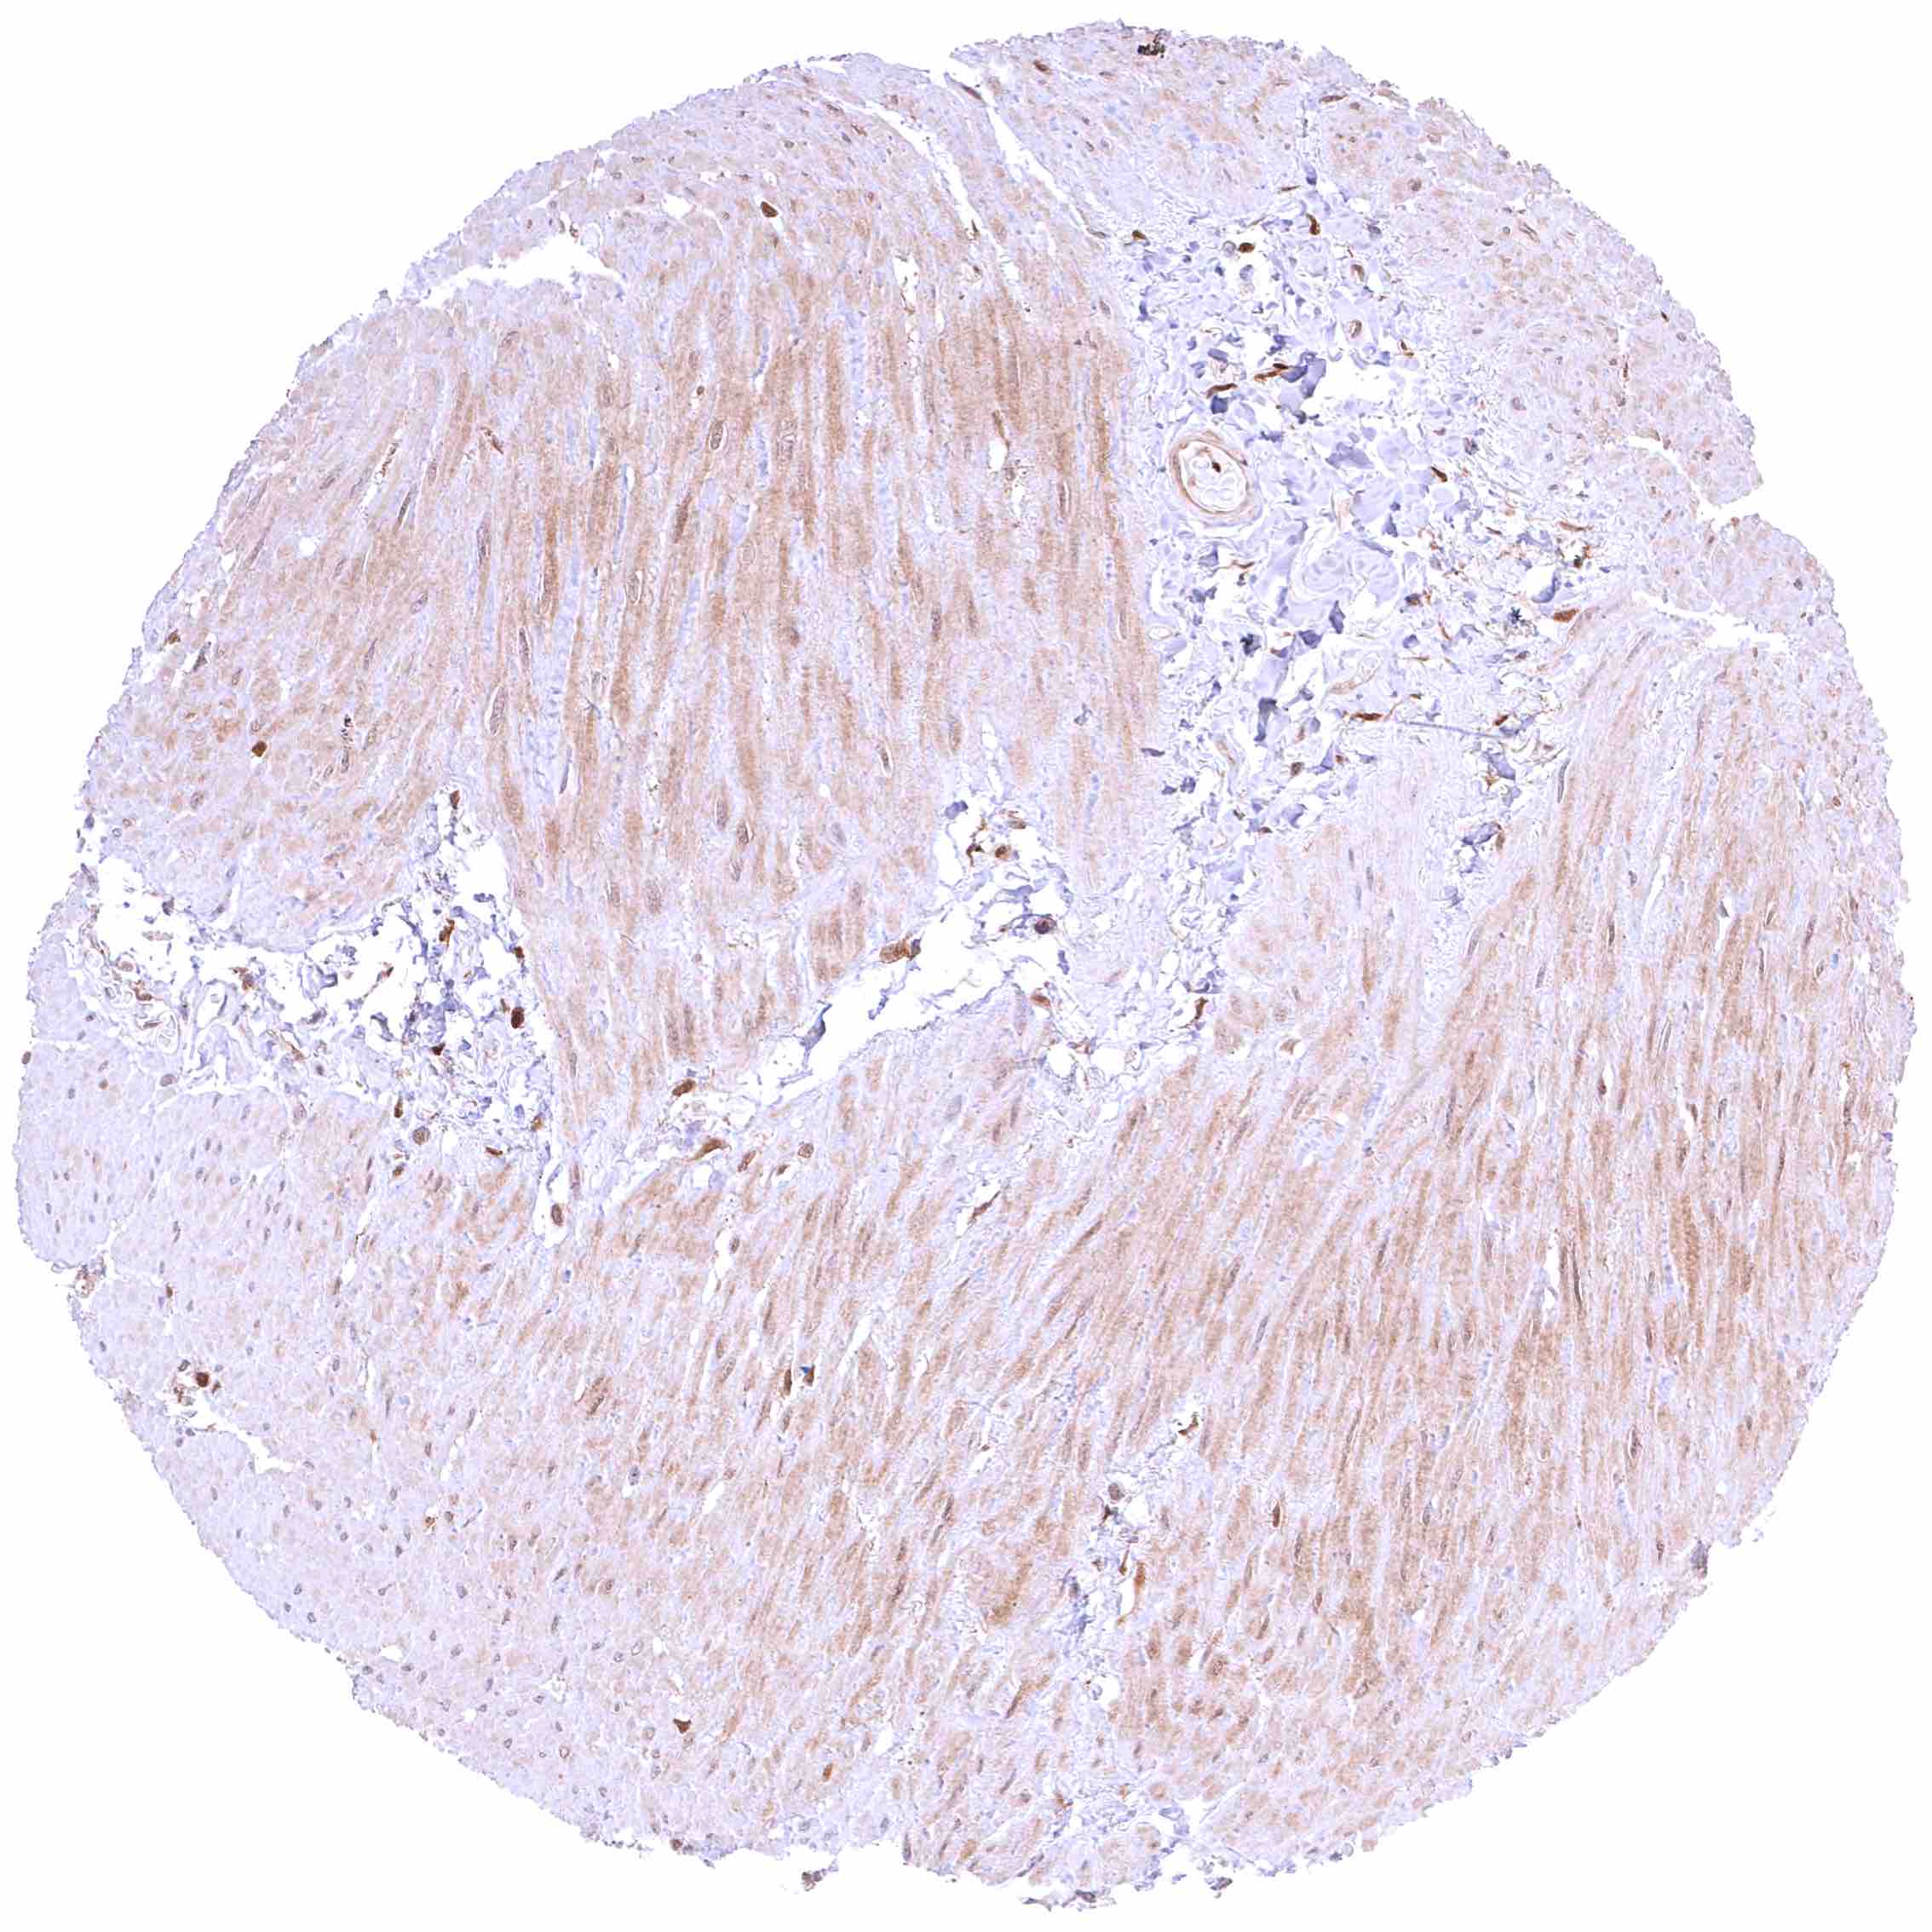

Skeletal muscle – Most GSTP1 staining occurs around small capillaries while the muscle cells are GSTP1 negative.